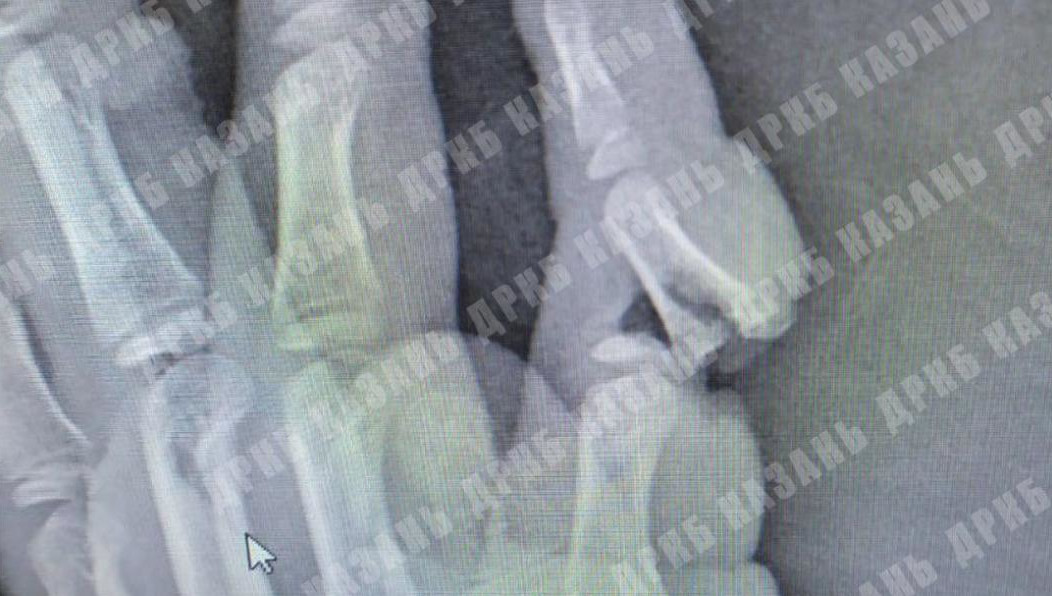

Мизинец держался только на лоскуте кожи, поэтому в травматологии ДРКБ ребенку выполнили остеосинтез – соединили отломки кости спицами, зашили рану подкожно. Помимо этого, у юного пациента были глубокие раны на поверхности ладони.